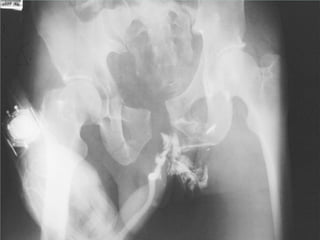

Fracture Pelvis

Associated injuries :

Head injury 51%

Extremity fracture 48%

Abdominal injury 28%

Peripheral nerve injury 26%

KUB injury 23%

Chest injury 22%

High mortality and morbidity rate

* 39% from hemorrhage

* 31% from associated injuries

* 30% from complications

Causes : traffic accident 84%

: falling from height 9%

: others 7%

Anatomy

Volume of Pelvis : ¶H( R² + 2Rr + r² )/3

R or r ↑ 2cm → vol. ↑ 1.3 litre

R or r ↑ 5cm → vol. ↑ 5.0 litre

3. Investigations

* pelvic film : AP , Inlet , Outlet , Judet